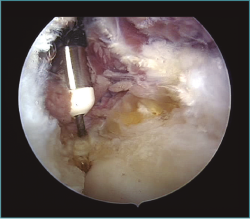

Figura 9. Caso 6. Corte de tomografía axial computarizada (TAC) de un paciente con rigidez postraumática con fractura osteocondral de cabeza radial y cóndilo humeral lateral.

Figura 10. Caso 6. Visión artroscópica desde el portal anteromedial del engrosamiento y la hipervascularización de la cápsula anterior del codo, responsable del déficit de extensión.